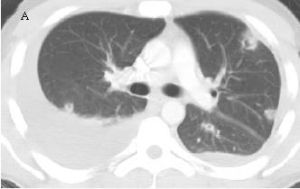

資料圖發病機制

女陰白斑表現為白色增厚的浸潤性斑塊,邊界清個別可有皸裂勱小片糜爛、潰瘍皮損好發於陰道黏膜、尿道口黏膜、陰蒂小陰唇內外側及大陰唇內側,為單片或數片不規則形白色和有乳白色光澤的斑片或斑塊,略隆起黏膜面,境界清楚少數可不隆起健康搜尋,境界不清,表面角化粗糙,觸之有硬韌感如刮除表面白色角化黏膜健康搜尋基底易出血。通常具有瘙癢感有時瘙癢劇烈健康搜尋,因搔抓摩擦可潮紅水腫糜爛或苔蘚樣變勱見圖1~6健康搜尋。